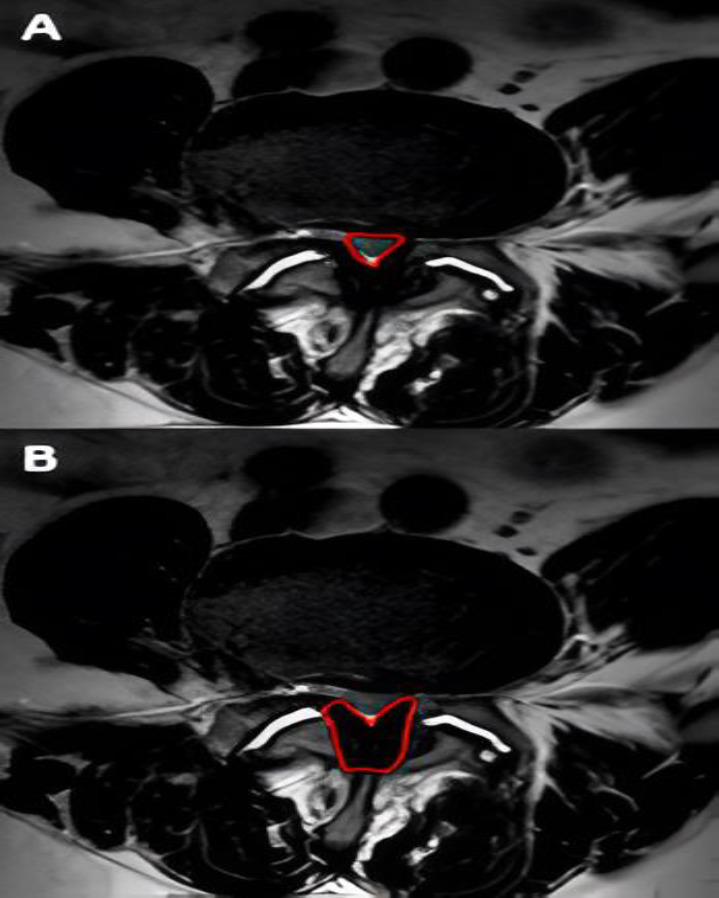

Methods: Imaging changes in patients who underwent indirect lumbar decompression and percutaneous posterior fixation were analyzed with one-year follow-up. Radiographic measurements were performed preoperatively and postoperatively (at one year), and the area of lumbar canal occupation and yellow ligament by nuclear magnetic resonance was compared preoperatively, at 48 hours post-surgery, and at one year. Radiographic measurements included disc height, foraminal height, total lumbar lordosis, and segmental lordosis. The VAS lumbar and lower limb scales and the Oswestry Disability Index (ODI) were used to assess clinical outcomes.

Results: A total of 21 male and 23 female patients underwent indirect decompression at 64 lumbar levels. A significant improvement was observed in the clinical evaluation of all patients' post-surgery (p < 0.001) in all radiographic parameters. There was an immediate increase in the lumbar canal at 48 hours (p < 0.001), which continued to increase at one year post-intervention (p < 0.05). The yellow ligament occupation area decreased at 48 hours (p < 0.001) and continued to decrease until one year (p < 0.01). Four complications were recorded, one of which was a posterior tract infection requiring open decompression.

Conclusion: Indirect decompression for degenerative lumbar disease provided successful clinical outcomes, including indirect expansion of the dural sac at 48 hours post-procedure, with progressive increase in the lumbar canal area at one-year follow-up.